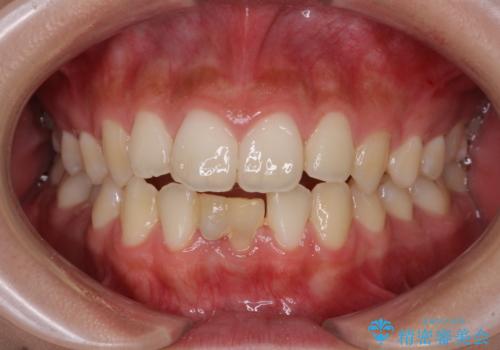

[ 前歯開咬 ] 前歯が噛んでいない マウスピース矯正治療

担当医 大元洋佑

![[ 前歯開咬 ] 前歯が噛んでいない マウスピース矯正治療の症例 治療前](https://seimitsushinbi.jp/wp/wp-content/uploads/2022/11/IMG_4669-500x350.jpg?v=1668218426)